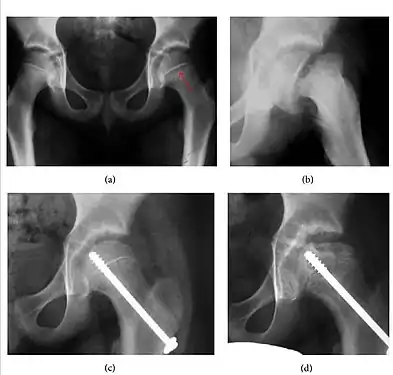

Synovial chondromatosis can be confidently diagnosed by X-ray when calcified cartilaginous chondromas are seen. However, other synovial proliferative processes, such as pigmented villonodular synovitis, require MRI for accurate diagnosis, although noncalcified synovitis can be suspected in radiographs by indirect signs, such as soft tissue swelling and/or erosions in the femoral head, femoral neck, or acetabulum (Figure 7).[1]

Figure 7:

Axial CT image of pigmented villonodular synovitis eroding the posterior cortex of the femoral neck.[1]

Sagittal T2* gradient echo image showing a posterior soft tissue mass with hypointense areas secondary to hemosiderin deposition.[1]

X-ray of synovial chondromatosis.[1]

CT of synovial chondromatosis.[1]